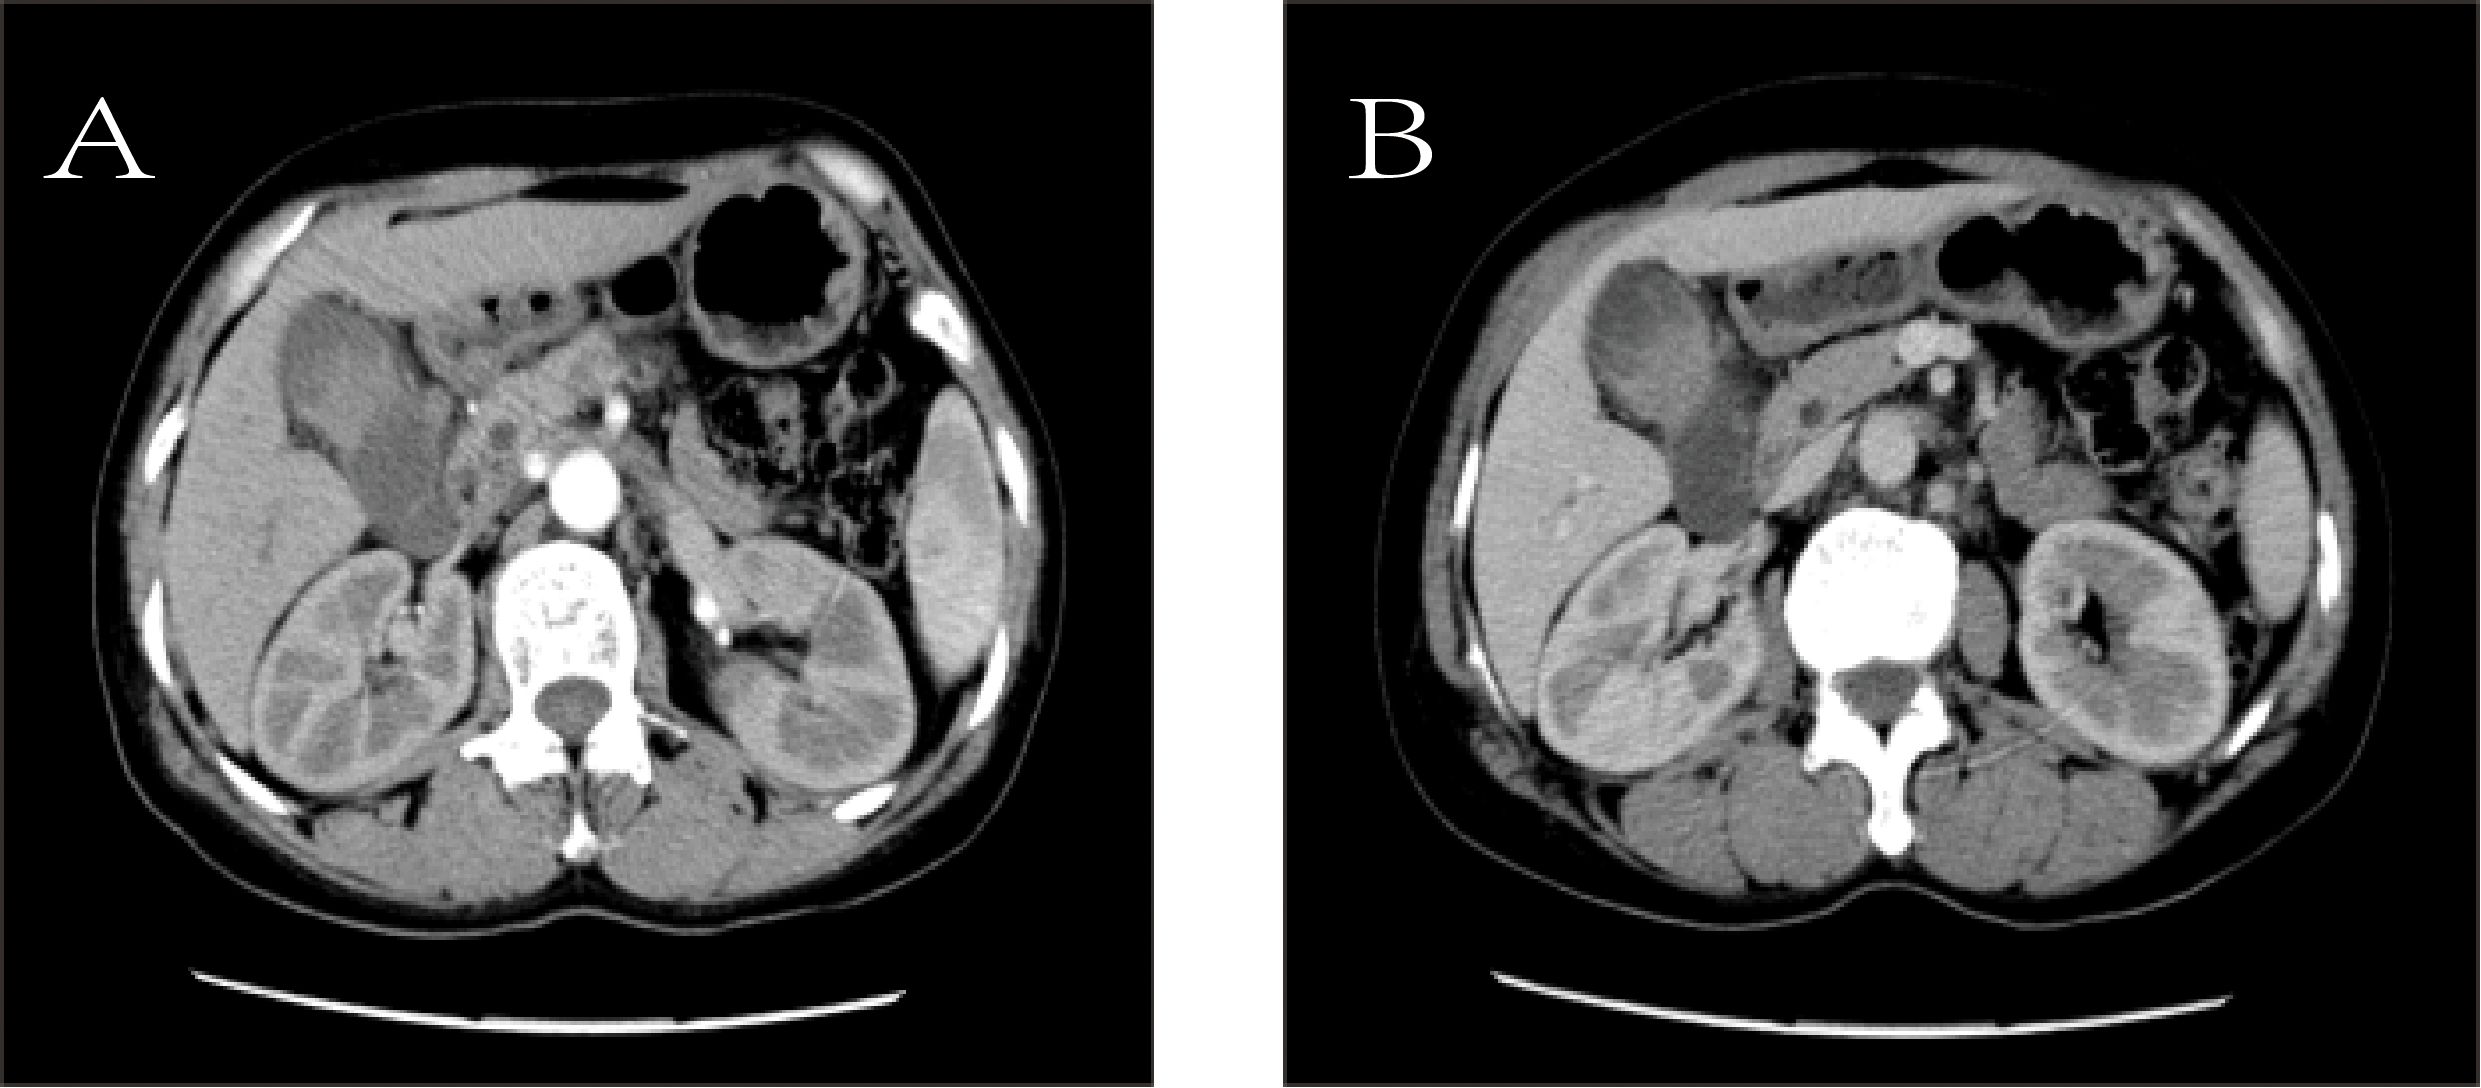

To further clarify the nature of the gallbladder mass, abdominal color Doppler ultrasound, upper abdominal contrast-enhanced CT, and PET-CT examinations were performed. Ultrasound revealed an enlarged gallbladder measuring approximately 9.7 × 4.2 cm with a moderately echogenic nodule filling its lumen, of indeterminate nature (See Figure 1). Contrast-enhanced CT showed increased gallbladder volume with localized uneven wall thickening and soft tissue density nodules protruding into the lumen, strongly suggesting neoplastic growth (Figure 2). Multiple nodular shadows were observed in the hepatic portal region, likely representing enlarged lymph nodes, with the largest measuring 1.9 × 1.7 cm. PET-CT confirmed increased retroperitoneal lymph nodes with elevated SUVmax values of approximately 18.0 and 25.9 on early and delayed imaging, respectively (Figure 3). These findings, showing both gallbladder soft tissue nodules and enlarged lymph nodes with abnormal metabolic activity, led to a preoperative diagnosis of gallbladder carcinoma with hepatic portal lymph node metastasis.

The gallbladder is enlarged and contains a soft tissue nodule measuring approximately 4.8 × 4.0 cm, which demonstrates markedly increased radiotracer uptake with a maximum standardized uptake value (SUVmax) of approximately 18.0 on early imaging and 25.9 on delayed imaging. An enlarged lymph node, approximately 1.8 cm in diameter, is noted in the hepatic hilum and also shows abnormally increased radiotracer uptake with an SUVmax of 6.9.

Figure 3. PET-CT.